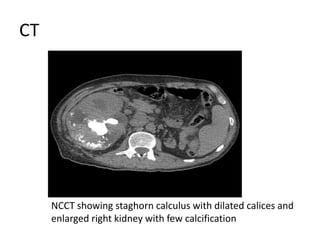

CT

NCCT showing staghorn calculus with dilated calices and

enlarged right kidney with few calcification